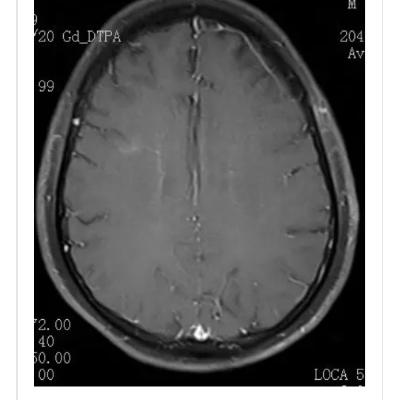

10月大婴儿,因癫痫持续状态就诊,2天前有发热和稀便。头颅MRI提示脑组织肿胀和累及丘脑,白质和背侧脑干的T2高信号病灶(图1)。丘脑病变在DWI和ADC上可见三层外观,伴有SWI上可见的局灶出血(图1-2)。 最终诊断:急性坏死性脑病 讨论 儿童急性坏死性脑病是一种爆发性脑病,主要累及婴幼儿。诱发因素包括病毒感染(流感病毒,轮状病毒,人类疱疹病毒6),免疫介导和遗传(RANBP2突变)。DWI和ADC上的三层表现和对称性丘脑受累具有特征性。